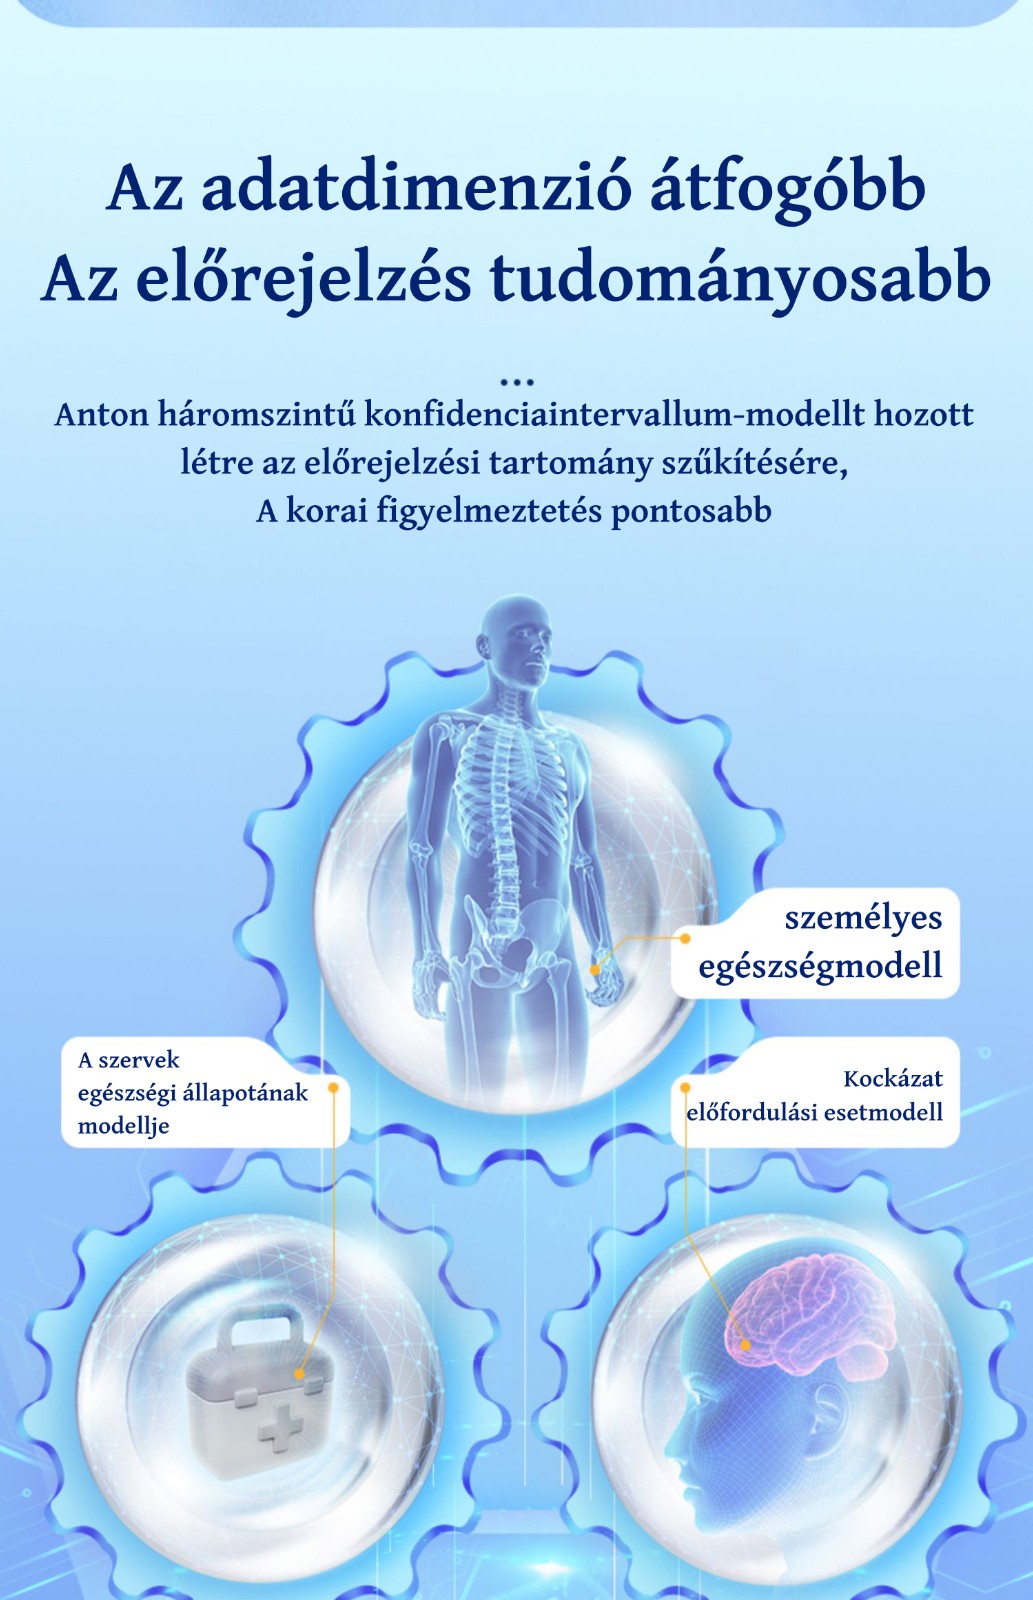

Nagy pontosságú intelligens egészségmegfigyelő óra

A szív- és érrendszeri és agyi érrendszeri betegségek "magas morbiditással, magas rokkantsággal, magas magas halálozási arány, magas kiújulási arány és számos szövődmény"

Orvosi és egészségügyi termékekre szakosodott technológiai vállalat vagyunk, és a termékfejlesztés terén régóta együttműködünk nemzetközileg elismert kórházakkal